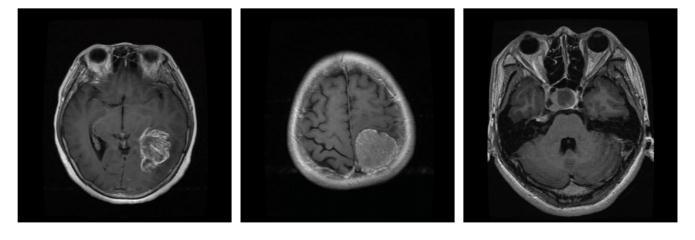

Fig - 1 : Flowchartofproposedmethod TheDatasetofbrainwithtumor: TheDatasetofbrainwithouttumor:

Fig - 2 : ImagePreprocessing OriginalImage CroppedImage Fig - 3:CNNmodelarchitecture Fig - 4:Trainingmodel